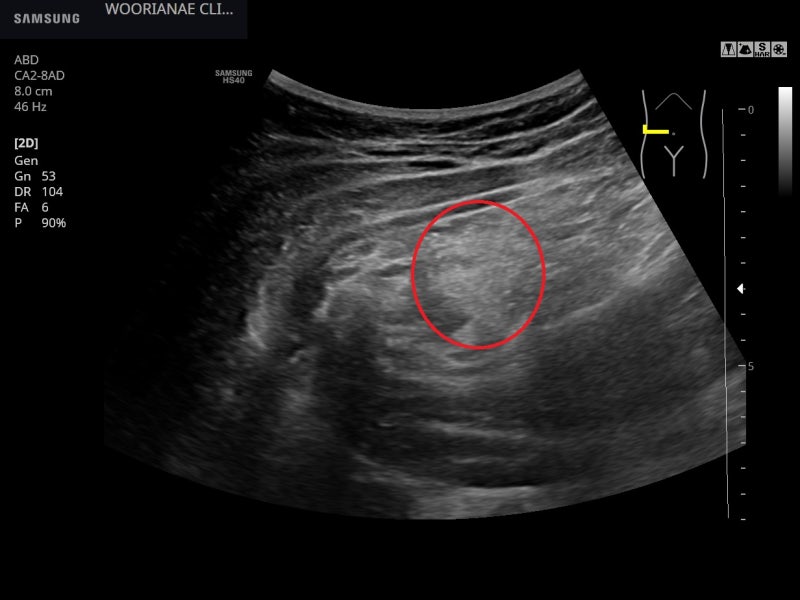

신체검사상 매우 명확하게 왼쪽 세 번째, 네 번째 sternocostaljoint에 국소적 압통 오래가는 증상에 대한 걱정도가 높다. 배제를 위한 심초코 및 연골 부위를 관찰한다.

프로브에서 누르면서 압통 부위를 확인할 수 있지만 연골 부위 소견은 명확하지 않았다.